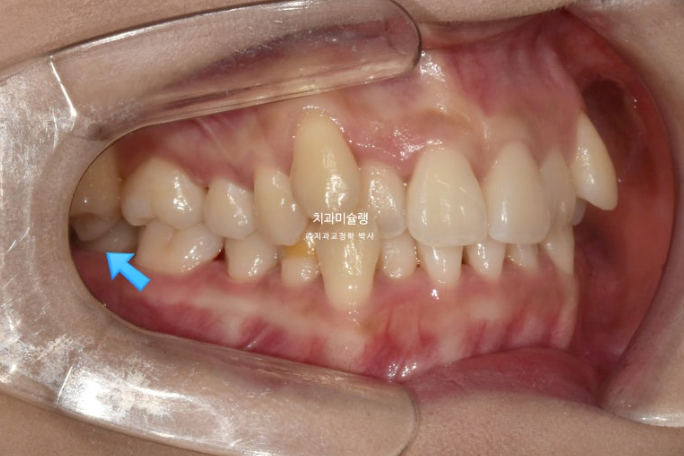

23.08

파란화살표는 가위교합입니다.

하지만 이 경우 맨 뒤 사랑니를 빼지 않고 파란 화살표 제2대구치를 발치했습니다. 발치한 제 2대구치 자리에는 사랑니로 대체해서 교정을 마무리 하는 방법입니다.

사랑니 대신 제 2대구치를 빼는 이유는 가위교합의 원인 치아를 제거하고 구치부 후방이동을 수월하게 하는 장점을 얻기 위해서이며 이 분은 맨뒤 사랑니가 두번째 큰어금니와 모양 사이즈가 동일했기 때문에 가능한 치료방법입니다.

즉 사랑니가 제 2대구치를 기능적으로 충분히 대체할 수 있는 상황